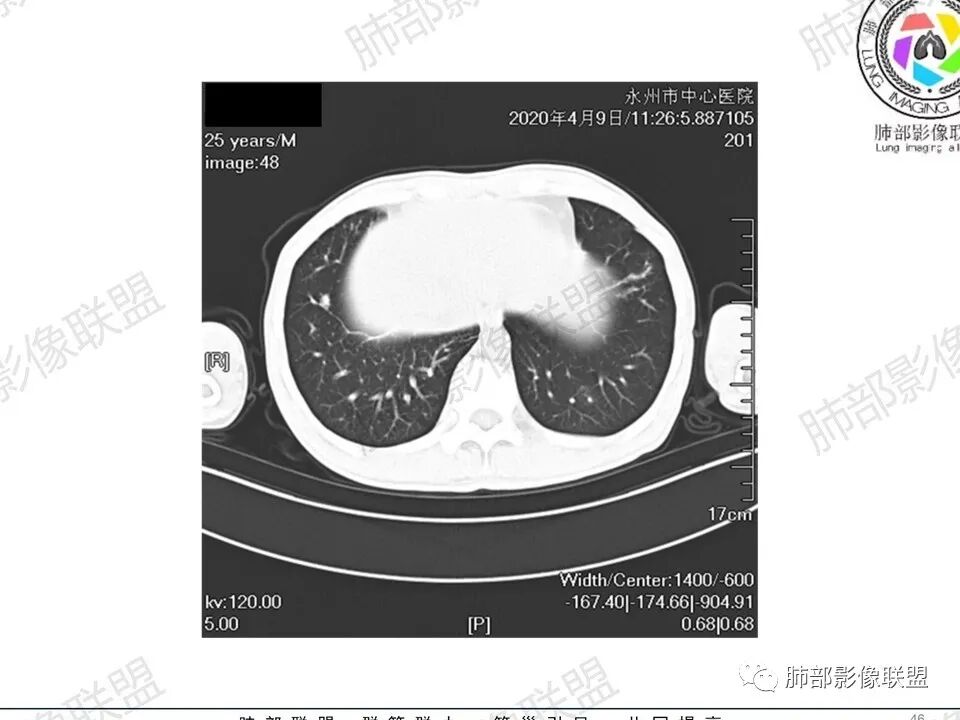

3、影像表现:双肺散在斑片影及结节影,部分结节内可见血管穿行,斑片影沿支气管血管束分布,近胸膜侧病变收缩不明显。部分中央淋巴间质增厚,小叶间隔增厚。病灶内支气管穿行,部分支气管略扩张。局部小结节呈串珠样改变。纵隔、肺门区、锁骨上及腋窝淋淋巴结肿大,部分有融合。心腔低密度。脾大。

2.双肺多发片影及结节影,边界可分辨,右肺中上叶较为密集,没有胸膜下分布优势。病灶实性密度为主,未见钙化及液化。

3.右肺较多微小结节,密度较为浅淡,部分沿血管束分布,未见沿小叶间隔及叶间裂分布结节影,未见典型的终末气道树芽。

4.病灶区域穿行支气管显示良好,未见壁增厚及管腔狭窄。

5.双肺门及纵隔淋巴结显著增大,这改变相当显眼。这里强调“双肺门”及“多发”!

增大的淋巴结密度偏低且均匀。此外患者有体表淋巴结增大。

淋巴瘤肺部浸润表现多样,多发结节影是其最常出现的影像学改变,尤其是霍奇金病。

2.右肺多发微小结节影,部分沿血管束分布,尽管未见小叶间隔改变,但双肺门淋巴结增大确实应当首先排除结节病,但经验上说,结节病的增大淋巴结密度往往较高、较密实,边界往往清楚,“独立性”很强,绝无“融合之嫌”!此外,较少出现贫血、脾大,临床表现也往往较轻微。